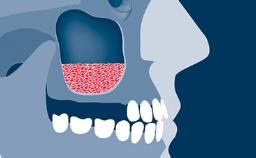

- describe how implant positioning can lead to esthetic complications

- describe other factors that may contribute to esthetic complications